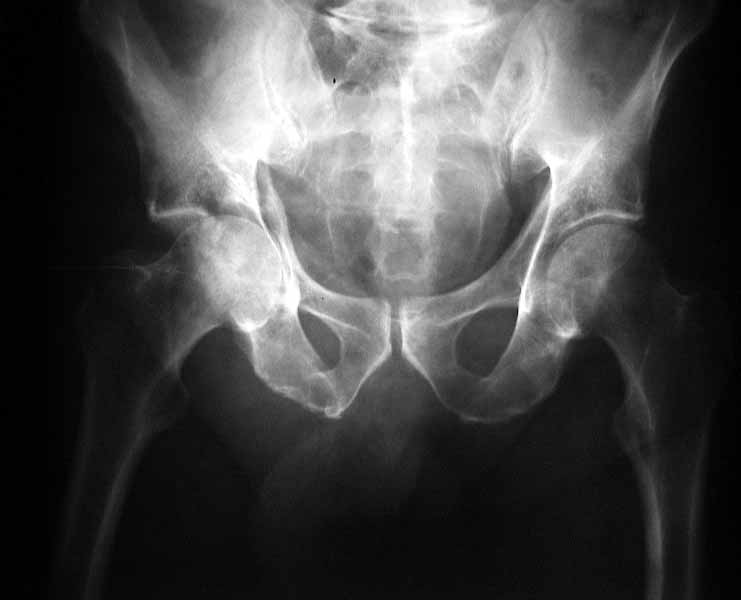

63 year old male, simple fall 4 days ago with an undisplaced Right Surgical neck of humerus fracture and this acetabular fracture. My assessment is that it is an anterior wall & column fracture with a blow out of the quadrilateral plate. the posterior column is intact. I see the immediate options as an attempted closed reduction and traction or an open reduction. I am right in saying this would need to be openly reduced through an ilioinguinal approach (which I have never seen or done). Or do I wait and do his Total Hip Replacement when his fracture has healed?

From: Peter Trafton

I agree with your diagnosis, and would suggest closed reduction under general anesthesia as soon as safe & convenient - distal traction, perhaps supplemented with lateral traction via a sheet looped around the proximal thigh. It would be nice to protect his articular surfaces with a reduction, even though it could prove unstable, even in skeletal traction, which I would use after the reduction attempt.